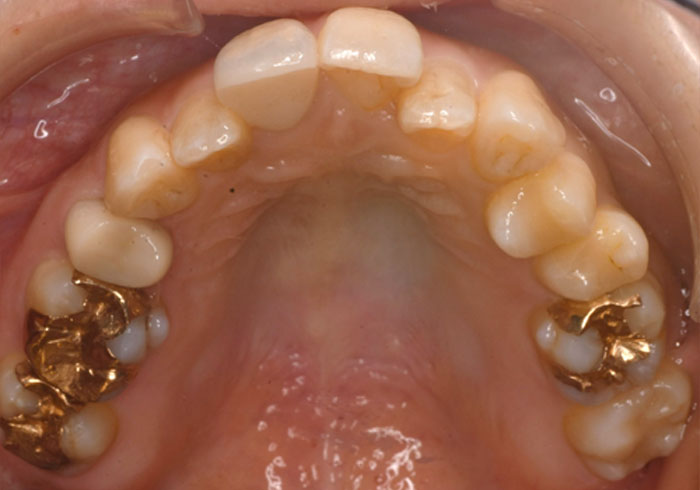

治療前

マウスピース矯正 マウスピース矯正 マウスピース矯正